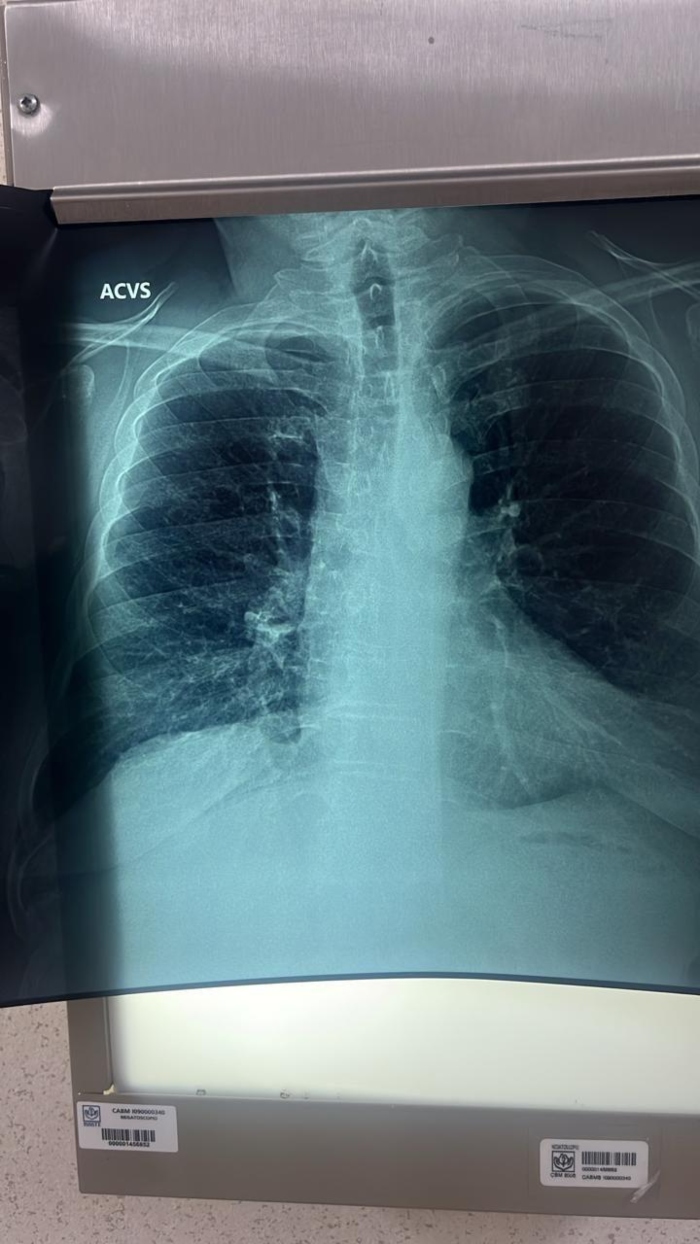

“Las consecuencias a nivel fisiológico son, en principio, la inflamación y obstrucción de los bronquios. En algunos pacientes puede llegar a producir enfisema pulmonar, es decir, la destrucción de las paredes de los alvéolos (pequeños sacos de aire en los pulmones) que provocan que los pulmones dejen de cumplir con su función principal: tomar oxígeno del aire para que llegue a la sangre y eliminar el dióxido de carbono del cuerpo”, detalló.

López de la Cruz indicó que, a pesar de que existen múltiples factores de riesgo que pueden provocar la EPOC, como la exposición al humo de leña —principalmente en comunidades rurales—, la contaminación del ambiente, secuelas de tuberculosis, asma mal tratado o alguna alteración a nivel genético, la principal causa es el tabaquismo.